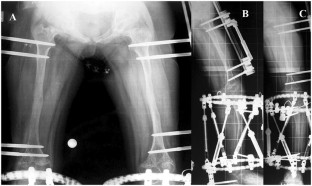

Fig. 4